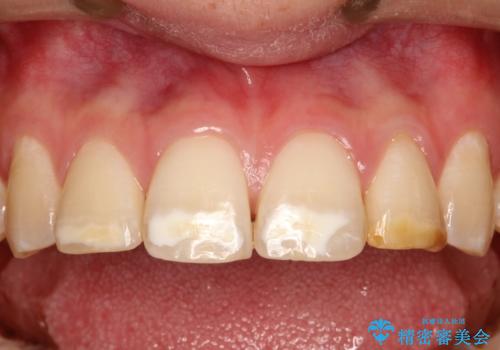

生まれつき歯の色が白濁しているところや、黄色くなっているところがあり、セラミッククラウンに審美的改善を行うこととしました。

ご自身の歯を削る必要がありましたが、セラミッククラウンを装着することで、審美的改善ができました。